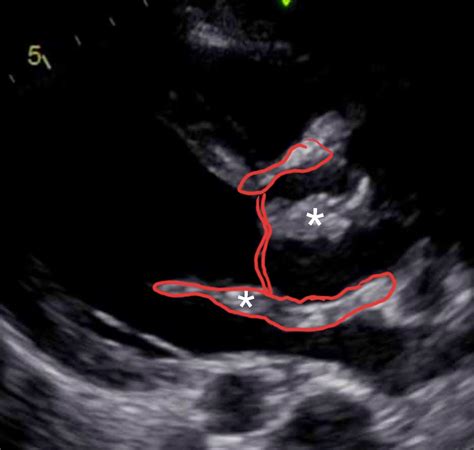

Hemispherectomy

Hemispherectomy is a surgical procedure in which half of the brain is removed. It is typically performed to treat severe epilepsy or other neurological conditions that do not respond to medication. The procedure can significantly improve the patient’s quality of life by reducing or eliminating seizures. However, it is a complex surgery with potential risks and complications.